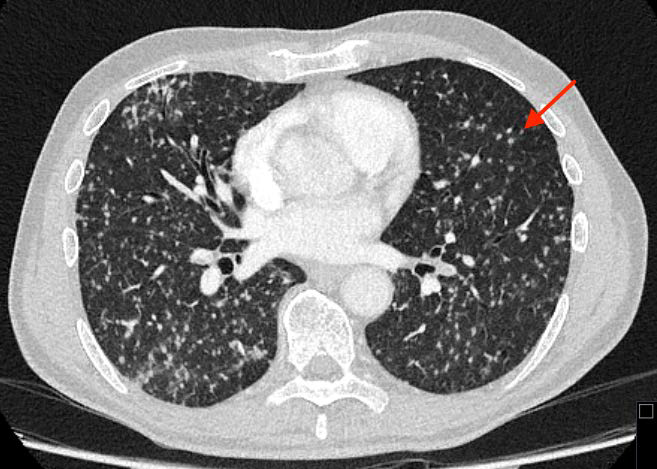

The Role of CT-Guided Optimal Fluoroscopic Projection Angle to Guide Stenting of Occluded Pulmonary Arteries

Yao Mi, MD, Mingwang Ding, MD, Yunshan Cao, MD, PhD

1-4